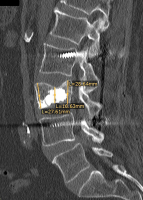

Möglichkeiten der direkten Zementinjektionstechnik bei Wirbelkörperfrakturen - Drei Fallbeschreibungen der Radiofrequenz-Kyphoplastie (RFK) mit ultrahochvikösem Knochenzement

Journal für Mineralstoffwechsel & Muskuloskelettale Erkrankungen 2012; 19 (3): 124-130 Volltext (PDF) Summary Praxisrelevanz Abbildungen